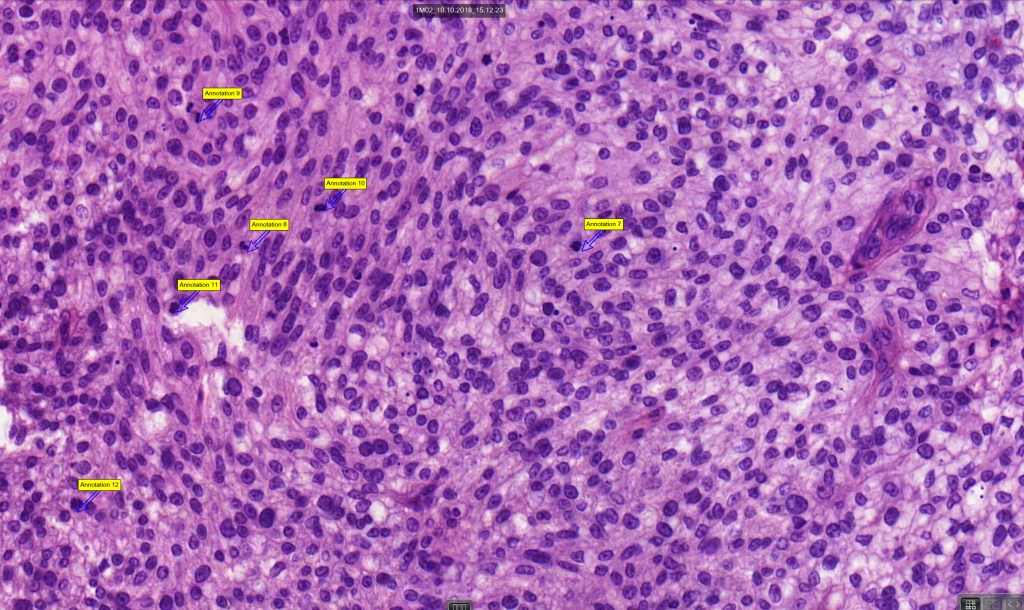

Histological features

•May affect the tumor in part or whole

•Enlarged cells with copious eosinophilic, foamy or clear cytoplasm (some authors include melanoma with clear cell change in the same category)

•Variable pigmentation

•Nuclei vesicular or hyperchromatic

•Pleomorphism is not generally marked and indeed can be very subtle

•Variable mitotic activity